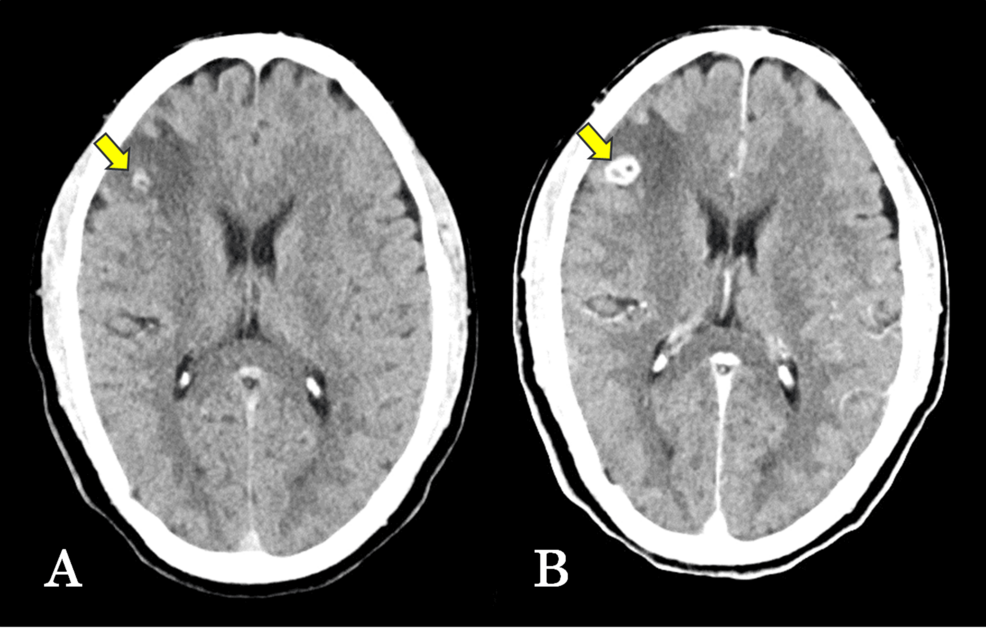

El caso presentado detalla la experiencia con un paciente que se presentó con síntomas neurológicos, lo que llevó a una evaluación exhaustiva para determinar la causa. El diagnóstico diferencial inicial consideró otras patologías más frecuentes en la región, lo que retrasó la identificación de la neurocisticercosis. Las pruebas de imagen, como la resonancia magnética (RM), fueron cruciales para detectar las lesiones características causadas por los parásitos en el cerebro.

El reporte subraya la importancia de considerar la neurocisticercosis en el diagnóstico diferencial de pacientes con síntomas neurológicos, incluso en países donde la enfermedad no es endémica, especialmente en individuos con antecedentes de viaje a áreas de riesgo o consumo de carne de cerdo poco cocida. Un diagnóstico temprano y preciso es fundamental para iniciar el tratamiento adecuado y prevenir complicaciones a largo plazo.